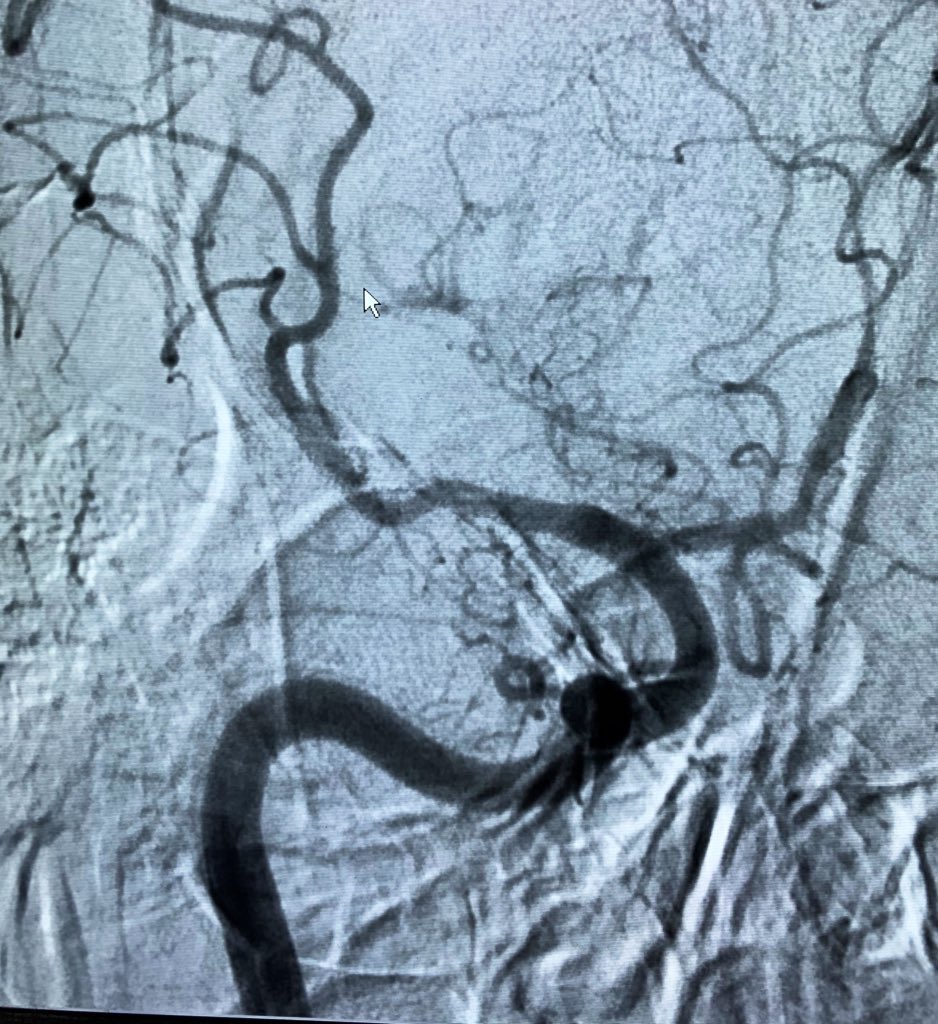

A quick case on Monday morning. Thrombus in the transition zone between M1 and M2.

#ADAPT with Sofia 5 FR.#thrombectomy@YoungNIR@LINNConline@ESOstrokepic.twitter.com/1nx2Bn3gX4